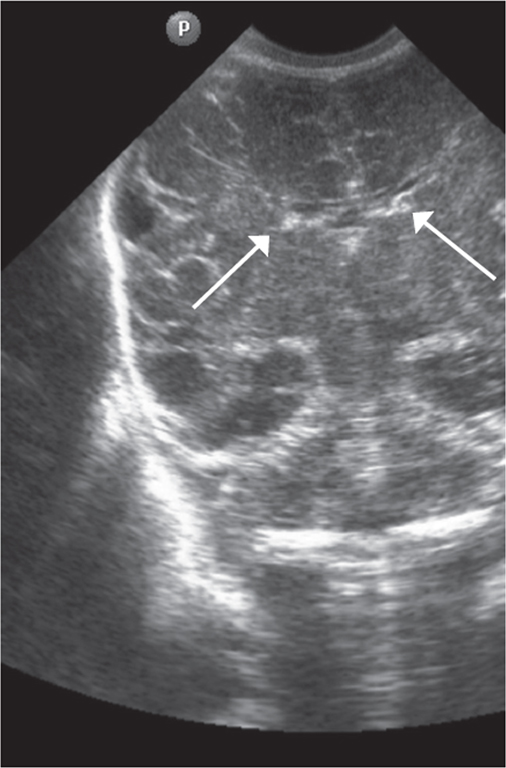

The first CUS was performed by using the anterior fontanel for all neonates (4 premature neonates in gestational week 25, 5 premature neonates in gestational week 26, and three premature neonates in gestational weeks 27, 28, and 29). Every preterm neonate underwent once daily ultrasound B brain scanning using the standard method with microconvex and linear transducers (5–7 Hz) [14]. Thickness of the visualized germinal matrix was measured in millimeters (mm) in the anterior horn of the lateral ventricles using the CUS (the Monro foramen projection, Fig. 1).

Fig. 1. CUS image of preterm newborn, gestational age 28 wks., frontal scan. Arrows indicate the area of visualization of the germinal matrix

Рис. 1. Краниальная сонография недоношенного новорожденного, 28 недель гестации, фронтальный скан. Стрелками указаны области визуализации герминального матрикса

In the present study, we showed that the sub-ependymal germinal matrix of the lateral ventricles could be detected using CUS in all premature neonates up to and including 29 weeks of gestation. According to K. Buch, the germinal matrix can be visualized as a hyperechoic structure in only 13% of infants up to 29 weeks of gestation [2]. We showed a regressive change in the sonographic imaging of the germinal matrix with increasing gestational age in all premature infants with ELBW. CUS showed a significant reduction in the size of the germinal matrix in premature neonates with ELBW up to and including 29 weeks of gestation.